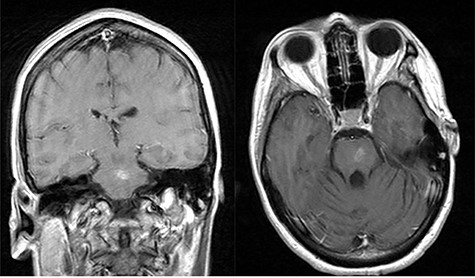

A 44-year-old female presented initially to an outside hospital with difficulty in speaking, right-sided facial droop and difficulty in walking. She also endorsed a 1-week history of intermittent headache. Magnetic resonance imaging (MRI) of brain demonstrated a ring-enhancing pontine lesion with surrounding vasogenic edema consistent with a brainstem abscess measuring 3.6 × 2.4 × 3.7 cm (Fig. 1a–c). There were no areas of ischemia. Pertinent history revealed no dental, cardiac or pulmonary source of infection. She had no history of intravenous drug use.

Pe-op axial, coronal and sagittal T1 post-contrast MRIs demonstrating rim-enhancing pontine abscess.